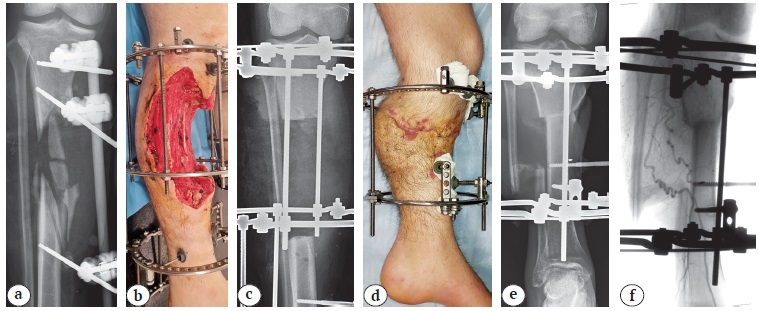

В группу II (38 сегментов) вошли наблюдения с протяженными дефектами большеберцовой кости и некрозами концов отломков большеберцовой кости, обширными дефектами мягких тканей, некрозами мышц в бассейне поврежденных артерий. Во всех случаях после ранения отмечалось нагноение ран. В результате проведенного лечения в 11 (28,9%) случаях удалось добиться купирования или существенного подавления местных гнойных процессов к моменту выполнения операции, направленной на укорочение. В 27 (71,1%) случаях вмешательство выполняли на фоне нагноения и фактически оно представляло собой вторичную ХО, а удаление некротизированной кости — основной элемент купирования гнойного процесса. Пример применения техники укорочения с резекцией концов отломков и постепенным их сближением представлен на рисунке 4.

Рис. 4. Пример применения техники подострого (постепенного) укорочения у пациента с осколочным ранением правой голени и оскольчатым переломом большеберцовой кости:

a — рентгенограмма в прямой проекции при поступлении (3-й день после ранения);

b — внешний вид раны через 7 нед.; после серии ХО дефект мягких тканей занимает 2/3 окружности и 1/3 объема голени на уровне верхней и средней третей; грануляции на всей поверхности;

c — рентгенограмма в прямой проекции через 7 нед., после резекции концов отломков и удаления некротизированных осколков между отломками имеется диастаз;

d — внешний вид через 9 нед., раны зажили, адекватную иммобилизацию обеспечивает аппарат из двух колец; e — на рентгенограмме в прямой проекции отмечается плотный контакт отломков, голень укорочена на 18 см;

f — ангиограмма через 7 мес. после ранения, отмечается деформация артерий на уровне верхней и средней третей голени

Figure 4. Example of applying subacute (gradual) shortening technique in patient with a shrapnel wound of the right lower leg and comminuted tibial fracture:

a — X-ray in the AP view upon admission (on the 3rd day after wounding); b — appearance of the wound in 7 weeks; after serial surgical wound debridement, the soft tissue defect occupies 2/3 of the circumference and 1/3 of the volume of the lower leg at the level of the upper and middle third; granulations on the entire surface;

c — X-ray in the AP view in 7 weeks, after resection of the fragments ends and removal of necrotized split-offs, there is a diastasis between the fragments;

d — appearance after 9 weeks, the wounds are healed, adequate immobilization is provided by a two-ring apparatus;

e — X-ray performed in the AP view shows a tight contact of the fragments, the lower leg is shortened by 18 cm;

f — angiogram performed in 7 months after wounding shows arterial deformity at the level of upper and middle third of the lower leg